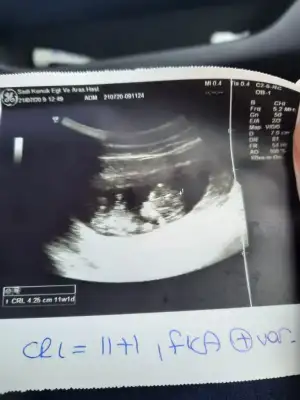

kızlarrr merhaba :KK200: bugun doktor kontrolüm vardı 2 li test için gittim cumaya randvu verdiler.

bebiş çok büyümüş. 14 gün geriden geliyordu 9 güne inmiş. normalde 12+3 haftalığım. 2 kilo aldım

bulantı kusmam yok. karnım da çıkmaya başladı. allahımm herkesin bebişleri çok iyi olsunnn... aminnn

cinsiyet tahminleri alayım :)